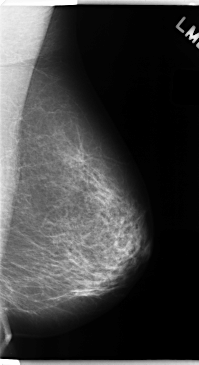

C_0151_1.LEFT_MLO

LEFT_MLO LINES 4736 PIXELS_PER_LINE 2584 BITS_PER_PIXEL 12 RESOLUTION 50 NON_OVERLAY